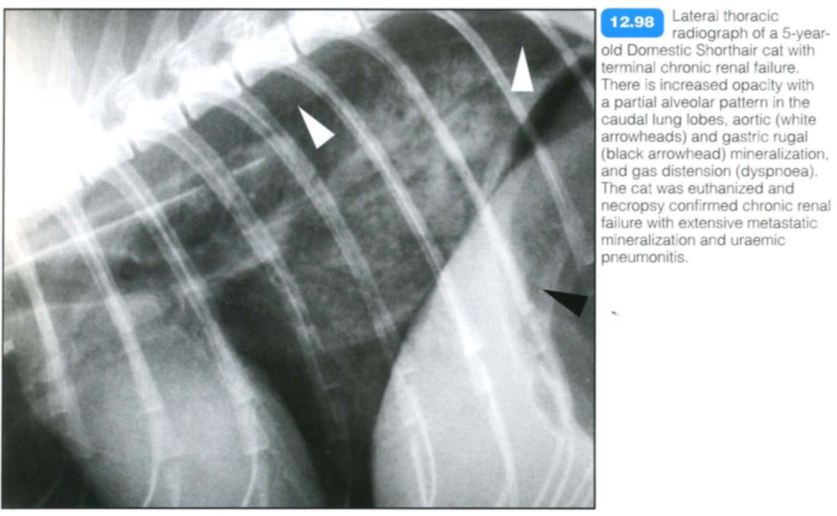

Uremic pneumonitis

Histopathological changes are similar to those of ARDS, and uraemic pneumonitis may be considered part of this syndrome. The high protein content of the oedema fluid suggests permeability oedema due to toxic lung damage. Other factors also are likely to play a role, e.g. reduced oncotic pressure and card io- vascular effects.

Clinical signs are related to severe renal disease (polyuria, polydipsia, anorexia, etc.) plus respiratory signs associated with oedema.

Uremic pneumonitis should be differentiated from other renal-induced respiratory diseases:

Radiographic findings include: